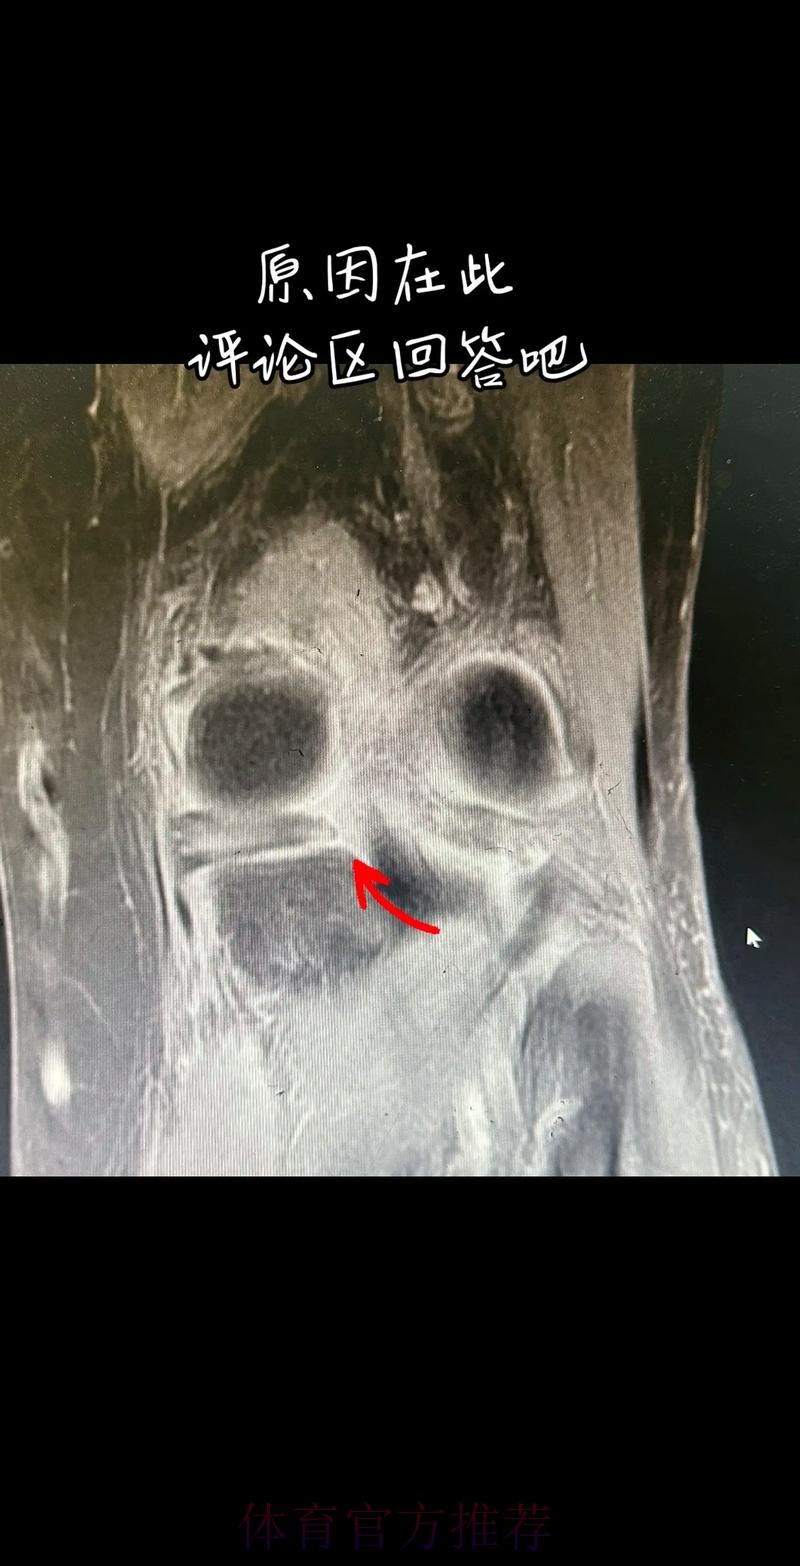

从医学角度看 半月板是膝关节内一块呈“C”形的软骨结构 其作用是缓冲冲击 稳定膝关节 并帮助分散压力 “左膝内侧半月板撕裂”通常说明在一次急停 旋转 或对抗中 半月板受到了超过其承受极限的力导致结构损伤 这类伤病常见于足球 篮球等需要频繁变向和对抗的项目 对于职业球员而言 半月板损伤严重程度不一 但共同点是都会影响支撑发力 跳跃以及变向时的稳定性 而官方给出的“预计伤缺6-8周”这个时间区间 往往对应的是中度损伤或通过微创手术加积极康复能够较快回归的情况 也意味着暂时没有出现必须长时间休战的最坏结果

表面上看 6-8周只是一个时间区间 但对顶级球队的赛程来说 这段时间可能包含多场联赛 甚至关键杯赛淘汰轮 相当于缺席一个赛季中最密集的一段周期 需要强调的是 这个“预计”并不是绝对数字 它取决于撕裂的位置 大小 修复方式 以及球员个体的恢复能力 有时若采取保守治疗 球员在6周时即可参与部分训练 但要达到比赛要求则可能接近8周甚至稍长 此外 精英运动员的康复不仅仅是伤口愈合 还包括力量恢复 协调重建 和心理自信的回归 阿拉巴要在有限时间内完成从“伤病患者”到“可靠首发”的角色转换 这一过程复杂程度远远超出一纸通告所能呈现